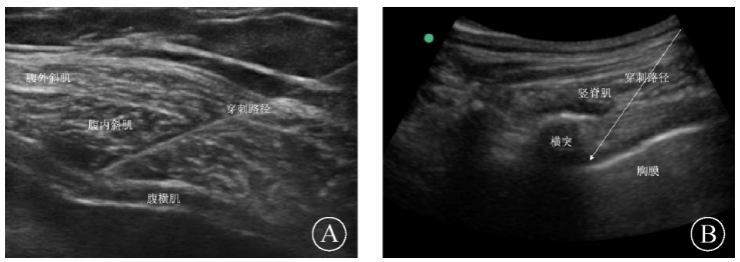

心脏移植术后并发带状疱疹性神经痛1例

病史摘要:62岁男性患者,因“扩张型心肌病,心功能Ⅳ级”行心脏移植术,术后使用他克莫司、吗替麦考酚酯等抗排异药物,并发急性肾损伤。术后第14天右侧T9神经支配区域出现带状疱疹,疼痛明显影响睡眠。诊疗过程:患者MMF减量,使用阿昔洛韦抗病毒,加巴喷丁、甲钴胺镇痛,局部涂抹利多卡因乳膏,并在CRRT治疗4小时后补充加巴喷丁。4天后疼痛缓解但仍有爆发痛,遂加用床旁神经阻滞治疗(腹横肌平面